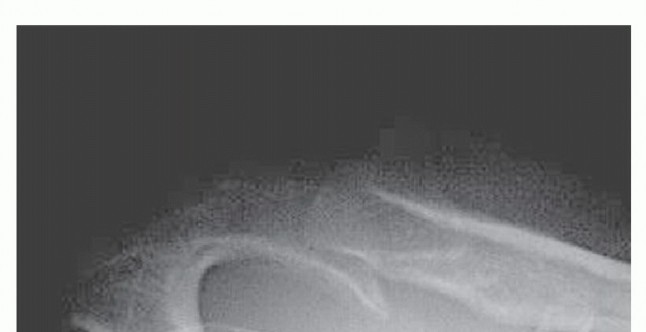

Arthroscopic Treatment of Subacromial Impingement DEFINITION Impingement syndrome was originally described by…